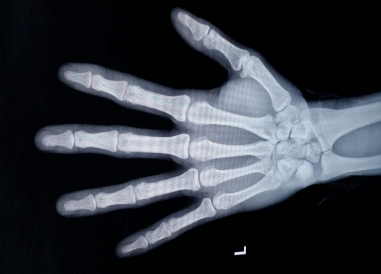

男孩子长高的时间一般比女孩子晚两年左右,十二三岁的时候开始迅速长高,到25岁左右才停止生长。不过要想更科学的知道自己还能否长高要去专业的医疗机构拍左手腕关节和骨盆的正位片,检测骨骺线是否闭合,若完全闭合就几乎没有增高的机会了。